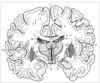

Key gyri on orbital view of frontal lobe

Gyrus rectus

Medial orbital gyrus

Anterior orbital gyrus

Posterior orbital gyrus

Lateral orbital gyrus

Key sulci on orbital surface of frontal lobe

Olfactory sulcus

Orbital sulcus